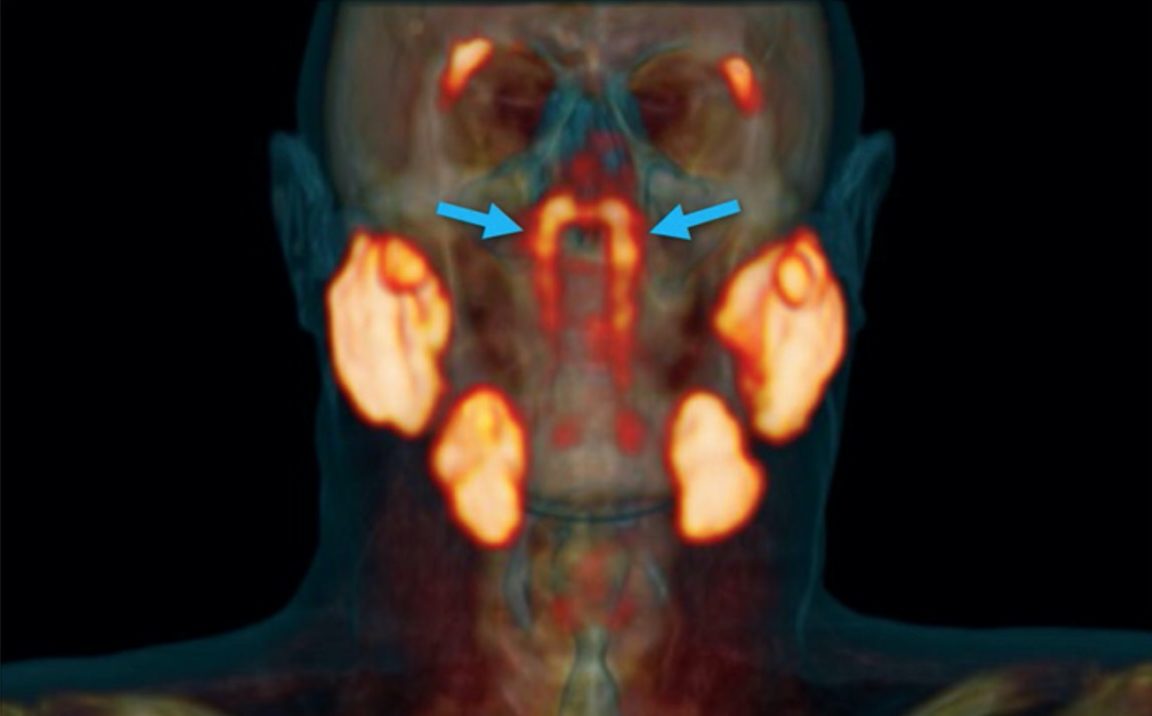

Plus récemment, des chercheurs néerlandais ont fait une découverte anatomique surprise, isolant ce qui semble être un nouvel ensemble de glandes salivaires nichées à l’arrière du nasopharynx.

Ces dernières auraient été identifiées alors que les médecins examinaient des patients souffrants d’un cancer de la prostate avec un PSMA PET-scan. Concrètement, cette machine, associée à des injections de glucose radioactif, permet de mettre en évidence les tumeurs présentes dans le corps.

Ceci dit, ce nouvel ensemble de glandes, isolées précisément derrière le nez et au-dessus du palais, près du centre de la tête humaine, appartiendrait à la première catégorie. Elles ont été nommées « glandes tubariennes » par les médecins, en référence à leur emplacement anatomique (au-dessus du torus tubarius).

La découverte de ces glandes tubariennes n’est pas un cas isolé. En effet, elles ont été observées dans les scans PSMA PET / CT d’une centaine de patients examinés durant l’étude. Elles ont également été identifiés sur deux cadavres – un homme et une femme.

Comment pourrait-on les avoir manquées durant tout ce temps ? Difficile à dire. Les chercheurs soulignent que les structures, situées sous la base du crâne, ne sont pas très accessibles. D’après eux, il serait même impossible de les distinguer par d’autres moyens que les nouvelles techniques d’imagerie PSMA-PET / CT. Il est également possible qu’elles aient été remarquées auparavant, mais finalement confondues avec d’autres ensembles de glandes.